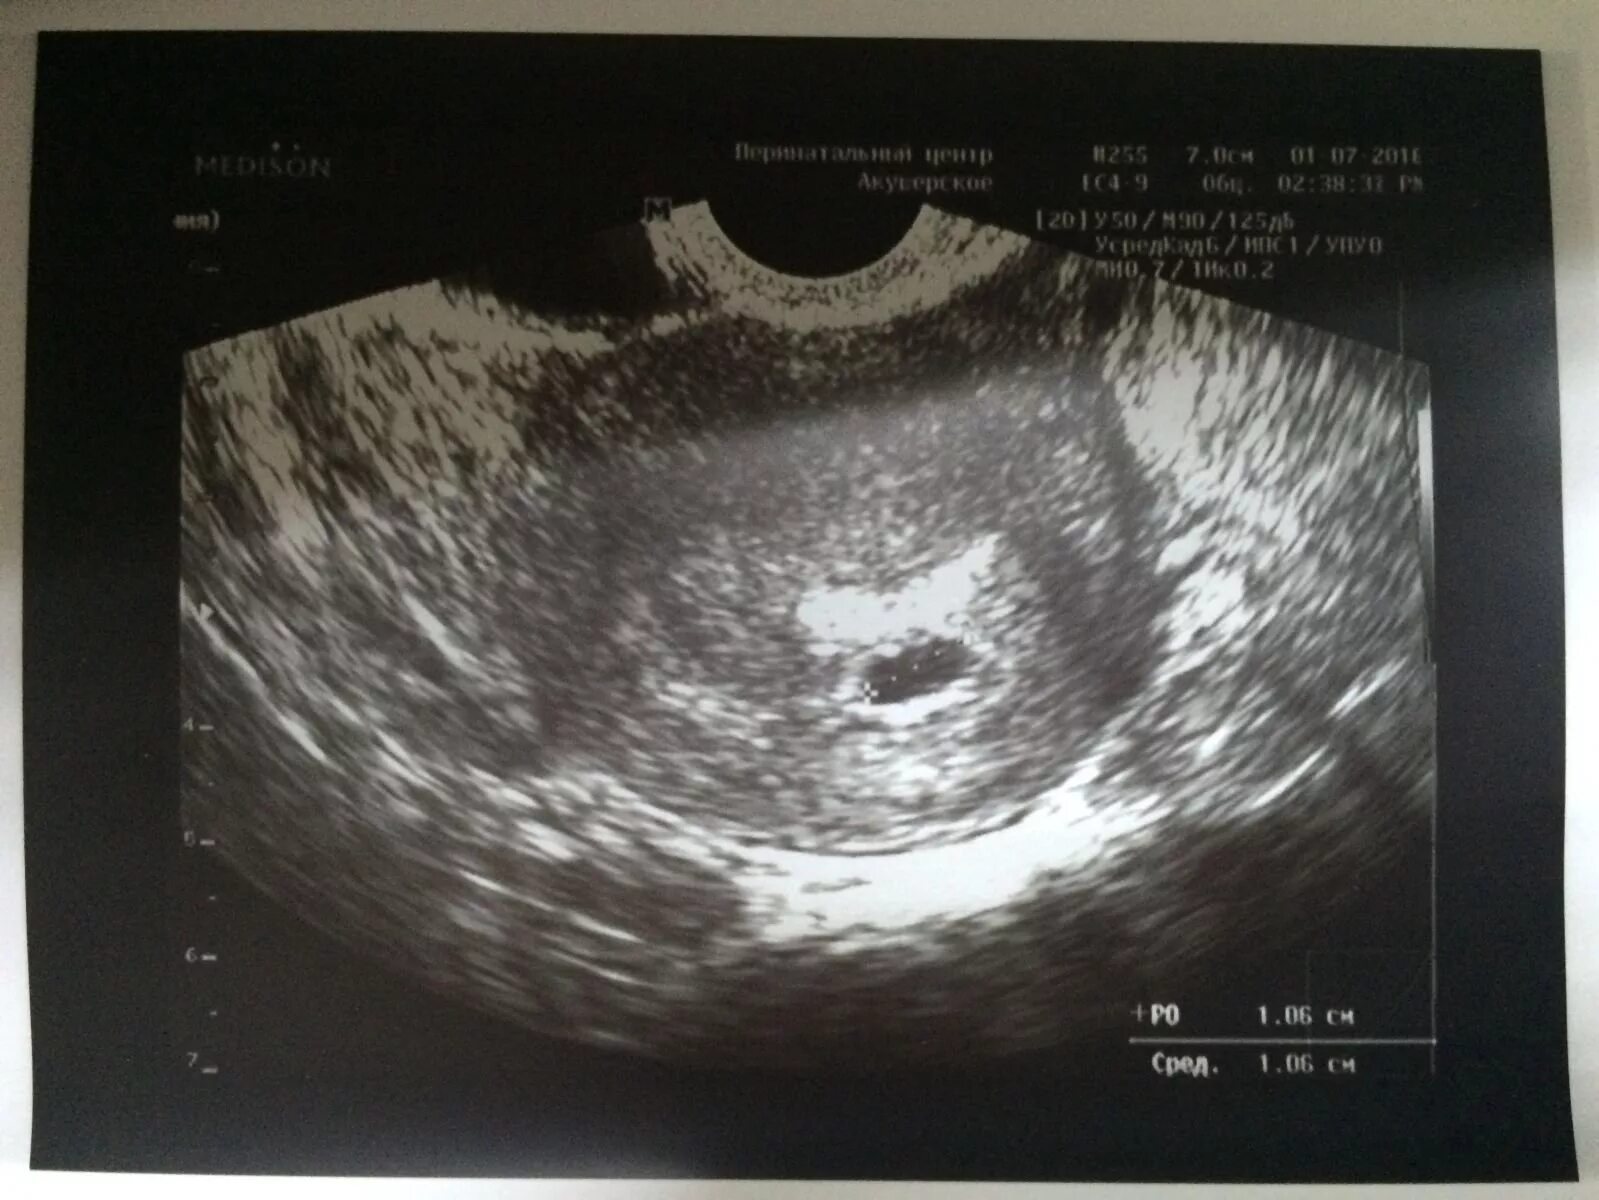

Плодное яйцо видно при хгч